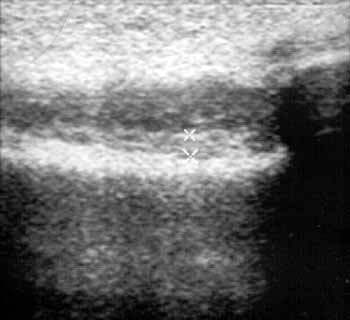

Рис. 3. Ревматоидный артрит, III стадия. Выраженное увеличение b. suprapatellaris

с наличием неоднородной жидкости и пролиферацией синовиальной оболочки (+).